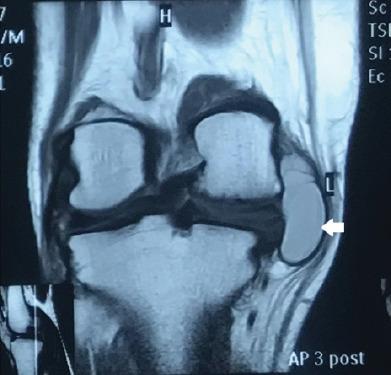

We report a case of a large symptomatic medial parameniscal cyst in 52-year-old female which was clinically misdiagnosed as Baker's cyst. The patient had swelling over the posteromedial aspect of the right knee with difficulty and pain on squatting. Magnetic resonance imaging (MRI) reported horizontal tear in the posterior horn of medial meniscus and parameniscal cyst adjacent to medial meniscus with features of early osteoarthritis of the knee. She was successfully treated with open excision and repair of the defect of the cyst along with arthroscopic partial medial meniscectomy.

This case highlights the importance of MRI in diagnosis and planning and the use of a combined approach for successful management of large parameniscal cyst.